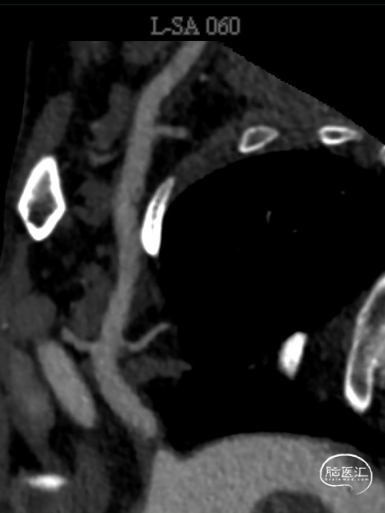

02、术前影像

1. 锁骨下动脉闭塞(左侧,伴盗血)

右侧椎动脉造影提示左侧锁骨下动脉盗血,左侧锁骨下动脉闭塞,近端残端较圆钝。

更换Supracore导丝,使用雅培 5*40mm Armada35 球囊扩张后在闭塞起始部植入8*29mm Omnilink支架。

使用雅培 Command导丝顺利超选进入左椎V2段,冠脉3.0*12mm球囊进行扩张,在V18导丝的支撑下,在左侧椎动脉起始部植入一枚雅培4.5*15mm Herculink支架。支架植入后,造影提示椎动脉狭窄得到明显改善。